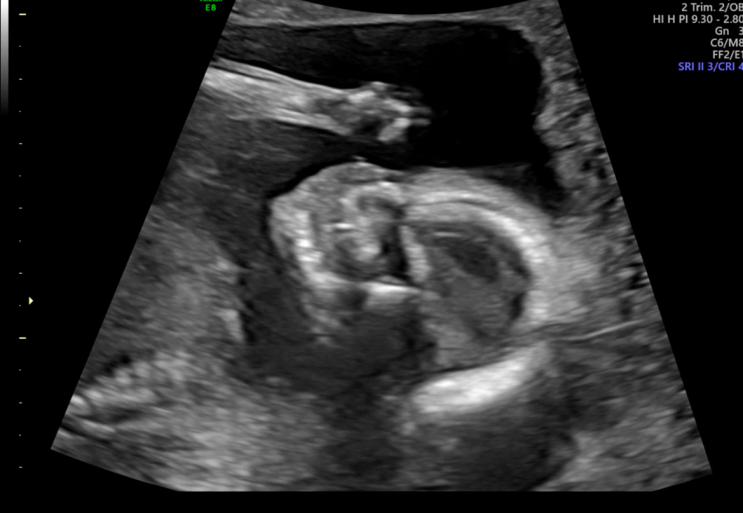

✨임신19-23주차일상/정밀초음파/전치태반/임산부수영/

20주-24주차에는 태아 정밀 초음파를 보는 시기예요 1차검진때 목투명대 등 기본 검사를 했다면 정밀초음파...